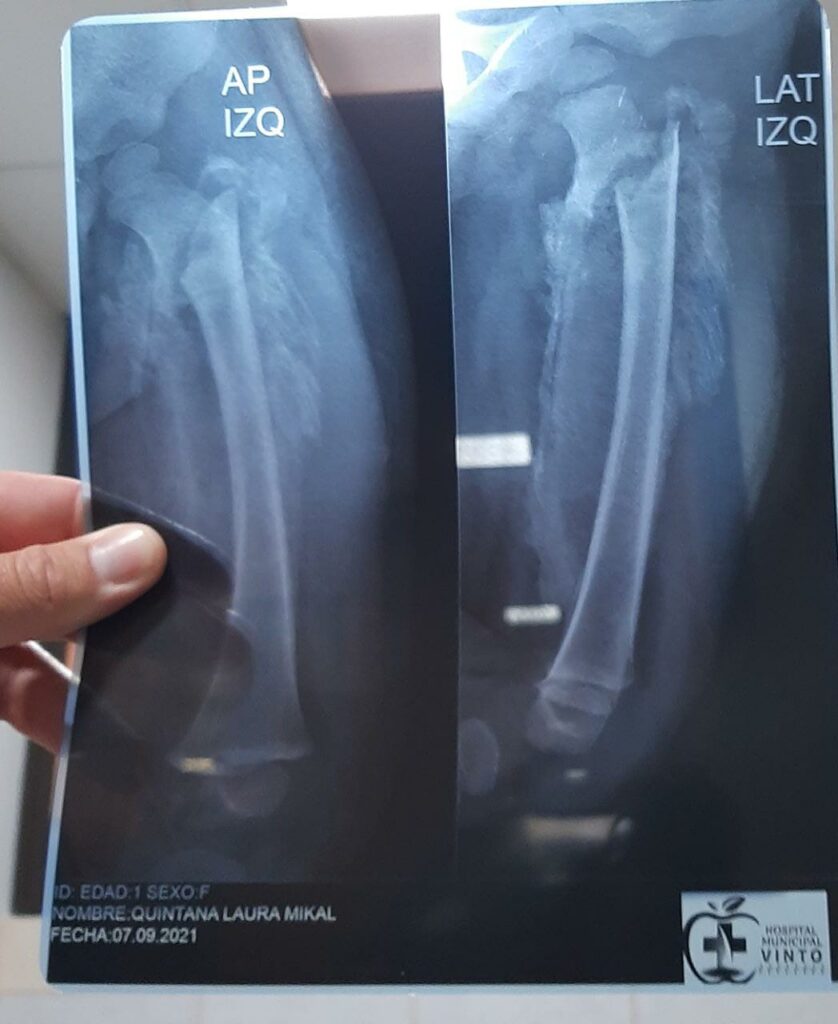

Bebita tiene múltiples fracturas

Una mujer y su hermana flagelaron a su hijastra, una bebita de tan solo 1 añito y 7 meses de edad, quién la tenía con las costillas fracturadas, la clavícula rota, las piernas fracturas, y la cabecita con severas lesiones, durante dos semanas, pues la víctima aguantaba los dolores sin poder caminar postrada en la cama.

La menor fue valorada y otorgada 140 días de impedimento, mientras las agresoras, fueron enviadas al penal de San Sebastián mujeres a la madrastra y a su hermana enviada a San Pedro por un lapso de 6 meses mientras dure las investigaciones antes de dar una sentencia por el delito de infanticidio en grado de tentativa.